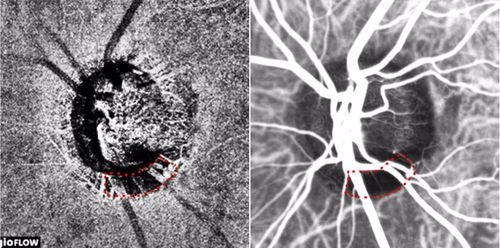

빛간섭단층 혈관조영검사(좌) 및 인도시아닌그린 혈관조영검사(우)로 얻은 녹내장 환자의 시신경유두 이미지. 붉은색 점선으로 둘러싸인 비관류 영역(혈류가 감소한 영역)이 일치한다(사진=분당서울대병원)

연구팀은 시신경 혈류 저하를 보인 녹내장 환자 30명을 대상으로, 기존의 침습적 검사인 인도시아닌그린(특수 형광물질로 조영제의 일종) 혈관조영검사와 빛간섭단층 혈관조영검사를 통해 각각 관찰한 시신경유두 이미지를 비교 분석했고, 그 결과 시신경 주위에 맥락막 혈류가 국소적으로 감소한 영역이 두 검사에서 일치한다는 사실을 발견했다. 이는 녹내장 환자의 시신경 혈류 저하를 관찰하는데 있어 비침습적 검사법이 기존의 침습적 검사 못지않게 정확하다는 의미다.